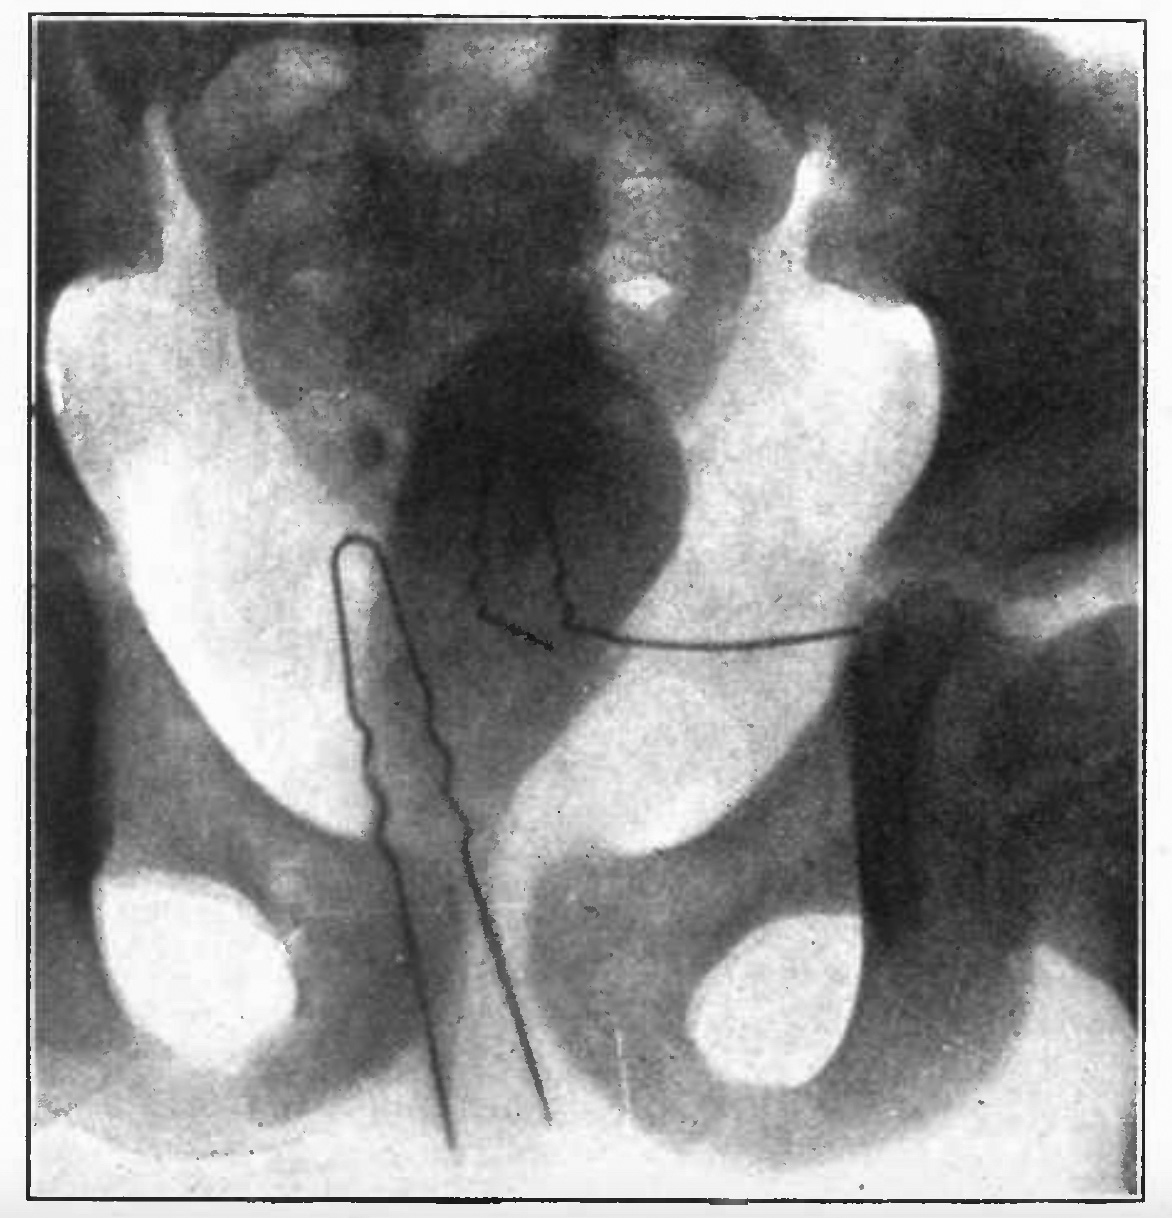

Pictured (right) is an X-ray showing two hairpins in the bladder of a young girl (Modern Urology - Cabot 1918: click the image for a larger, resizeable view).